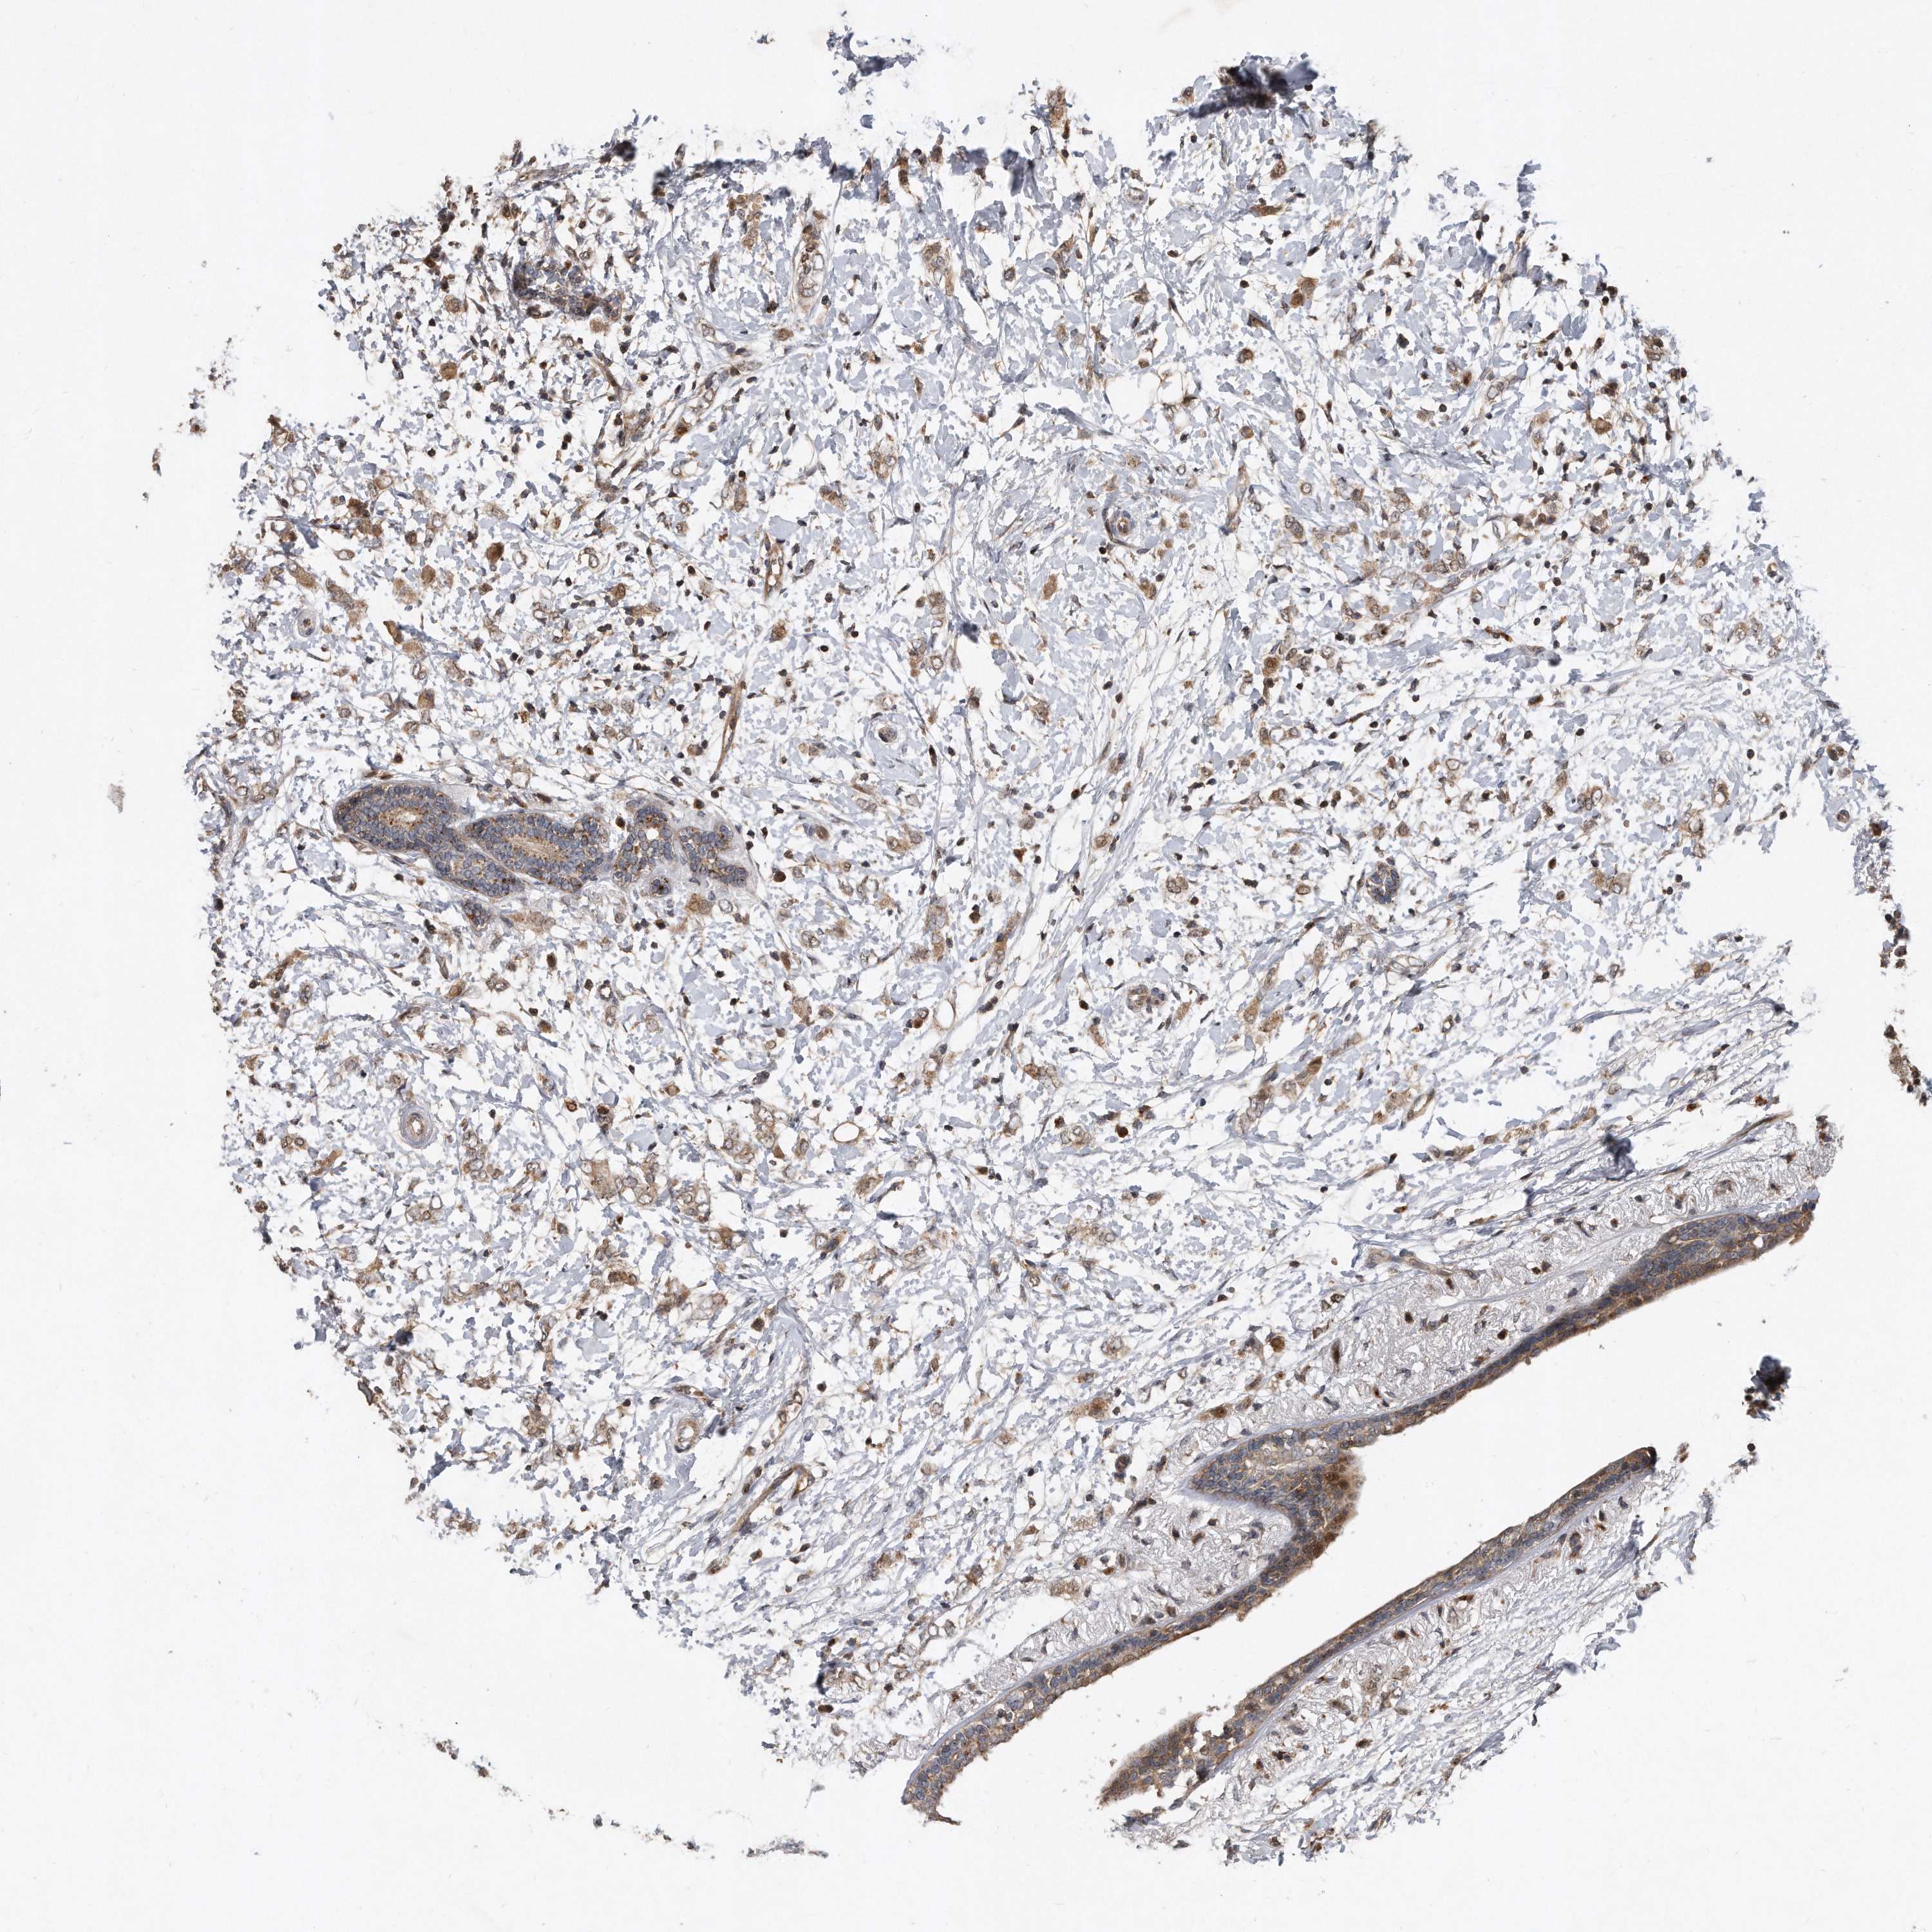

BRCA TCGA BRCA VALIDATION PROTEIN EXPRESSION

ANTIBODIES

AND

VALIDATION